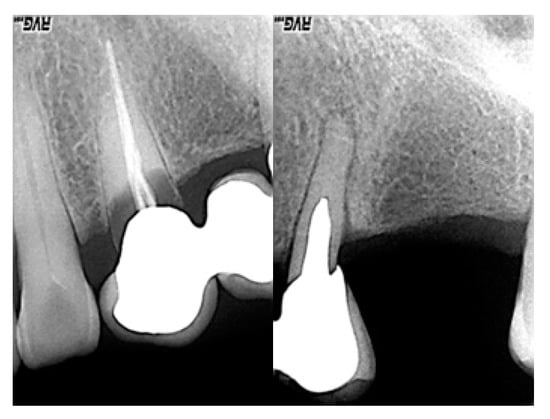

Clinical examination: the intraoral examination shows an absence of 2.6 and a fixed prosthesis in the area of 2.3–2.5.

Intraoral X-ray examination: the lack of integrity and inconsistency of 2.3 and 2.5 (pillar elements of the fixed prosthesis) are highlighted (Figure 4).

Figure 4. Preliminary radiographs.